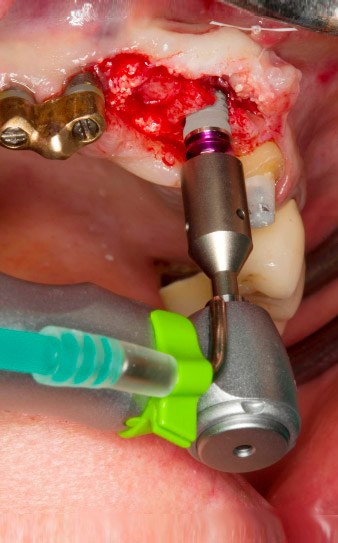

След първичното оздравяване, меките тъкани са оформени посредством базално разположения мост. Два месеца по-късно, обработваното поле е изложено на палатинална алвеоларна инцизия (Фиг 2). Размерите на алвеоларната кост са достатъчни в позиция 22. Фигури 2 и 4 показват препарацията на имплантното ложе, нарязващия винт и имплатирането, използвайки Implantmed.

пилотното изпиляване е извършено с новия Implantmed и обратен наконечник WS-56 L

Фиг. 2: Два месеца по-късно, пилотното изпиляване е извършено с новия Implantmed и обратен няконечник WS-56 L (програма P1, съотношение 1:1). Охлаждането е е осъществено чрез шлауха за физиологичен разтвор, позициониран отляво (за потребители, работещи с дясна ръка).

Нарязване с винт с обратен наконечник WS-75 L

Фиг. 3: Нарязване с винт с обратен наконечник WS-75 L със съотношение 20:1 (програма P4). Високият въртящ момент на Implantmed, хексагоновата система на цангата за надеждно предаване на мощноста и автоматичното обръщане на посоката на въртене, когато съпротивлението стане твърде голямо, са особено полезни в този случай.